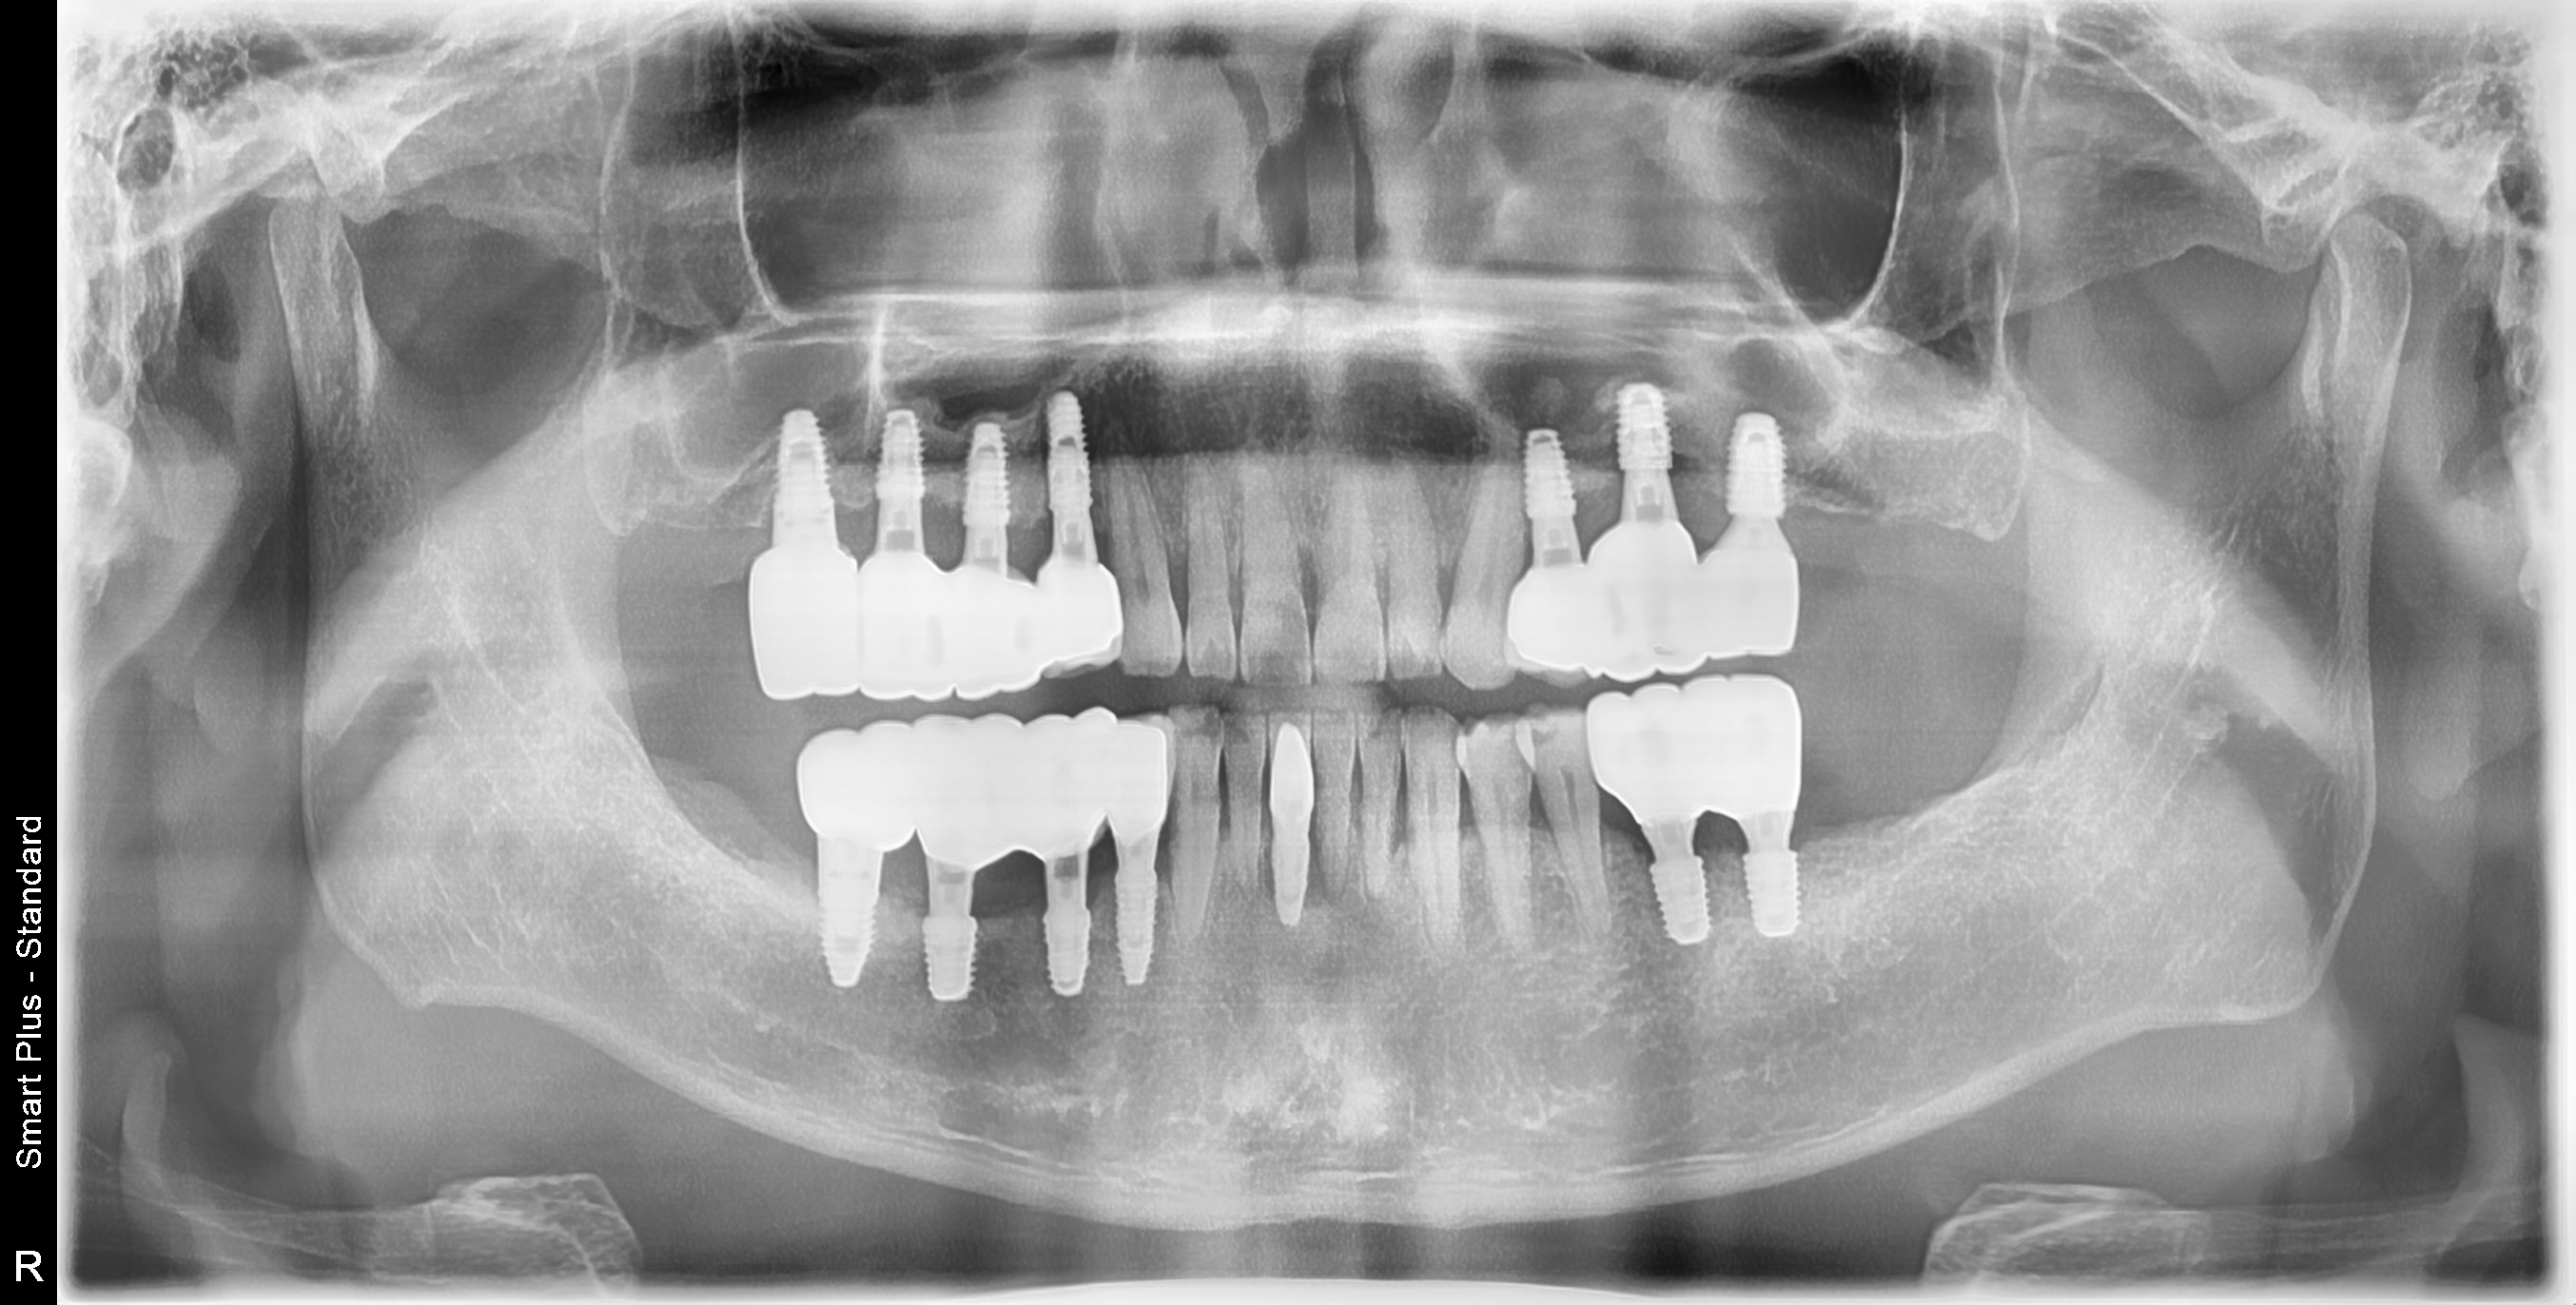

[임플란트] 제목 : 치주환자의 임플란트 보철치료

50대 치주환자의 임플란트치료.